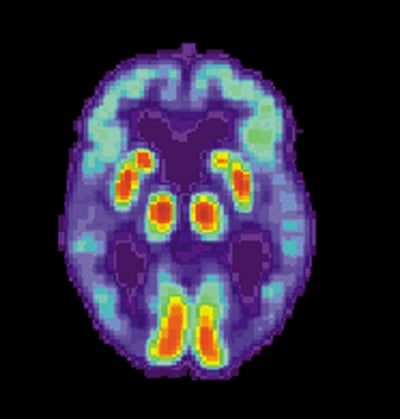

US National Institute on Aging, Alzheimer's Disease Education and Referral Center,

Public domain, via Wikimedia Commons